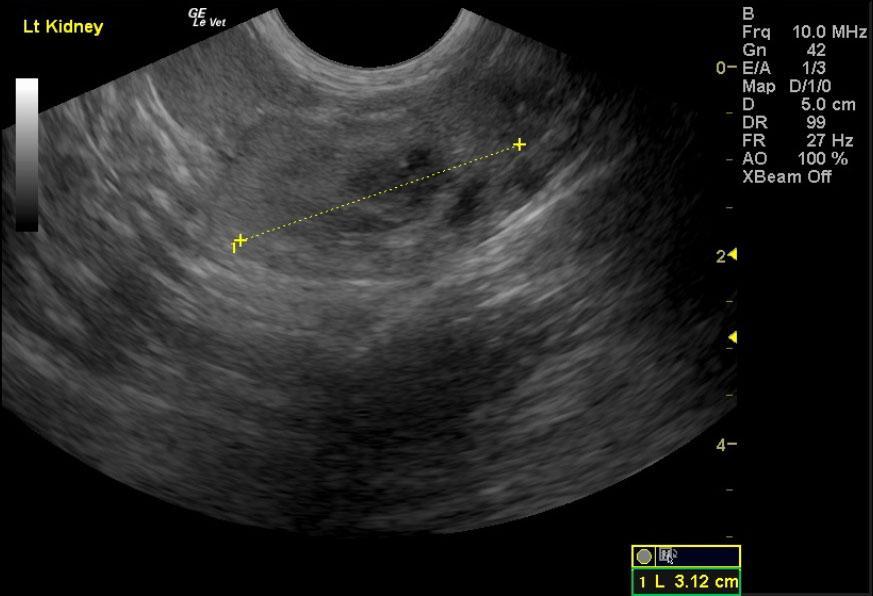

A 17-year-old neutered male DSH cat was presented to the emergency clinic with open-mouth breathing suspected to be secondary to stress/pain as the patient improved on analgesics. On a prior physical examination, an abdominal mass had been palpated.